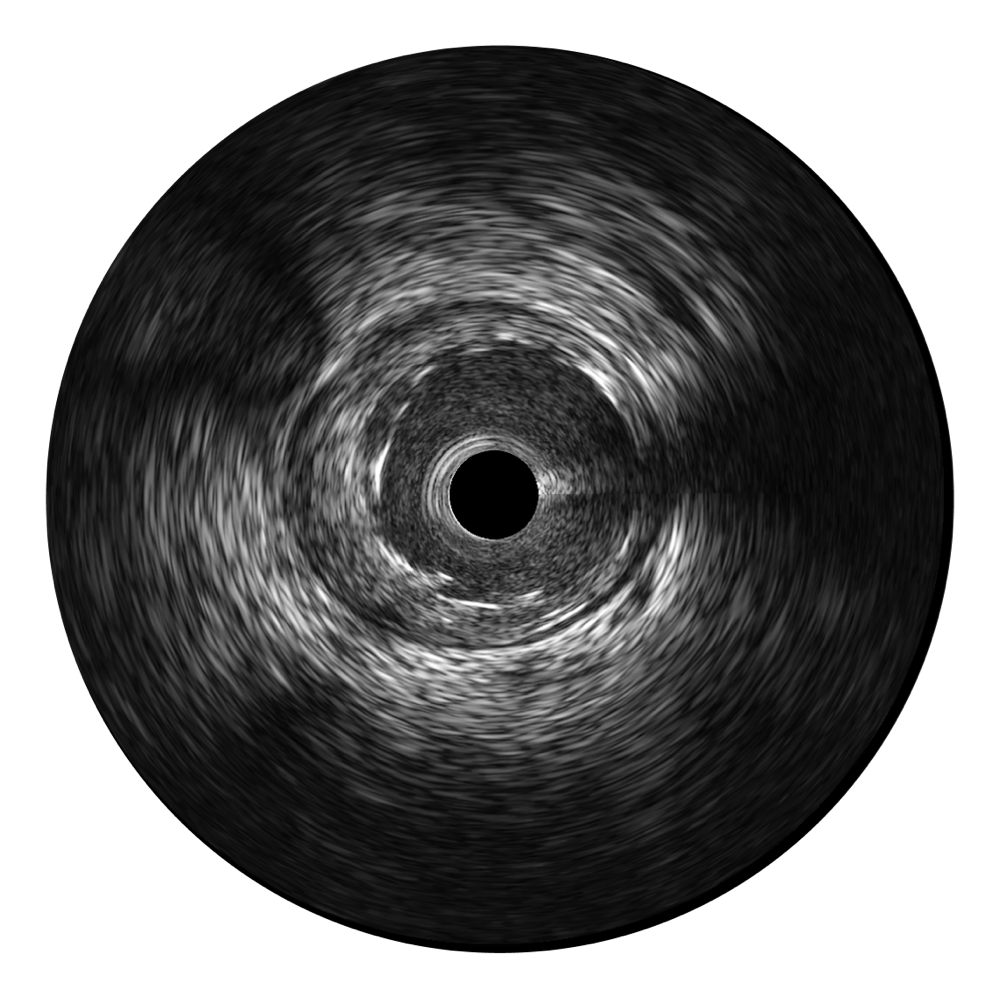

開立寬頻IVUS圖像

傳統(tǒng)IVUS圖像

對比傳統(tǒng)IVUS導(dǎo)管成像,開立寬頻IVUS圖像的近場支架梁顯影更細(xì)膩,遠(yuǎn)場中膜外血管仍清晰可辨,兼顧遠(yuǎn)中近,兼顧分辨力與穿透深度